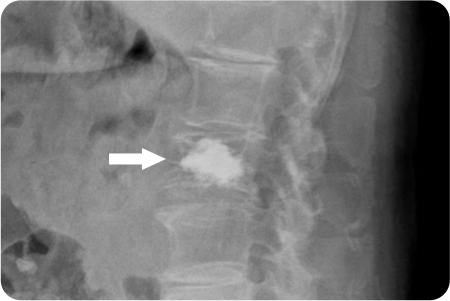

3

관절경하

척추체 성형술

피부에 작은 절개를 내고, 가느다란 바늘을 통해

골절된 척추 뼈 내부에 접근합니다. 골절된 척추 뼈

내부에 특수 의료용 시멘트(골시멘트)를 주입하여,

뼈를 단단히 고정하고 통증을 줄입니다.